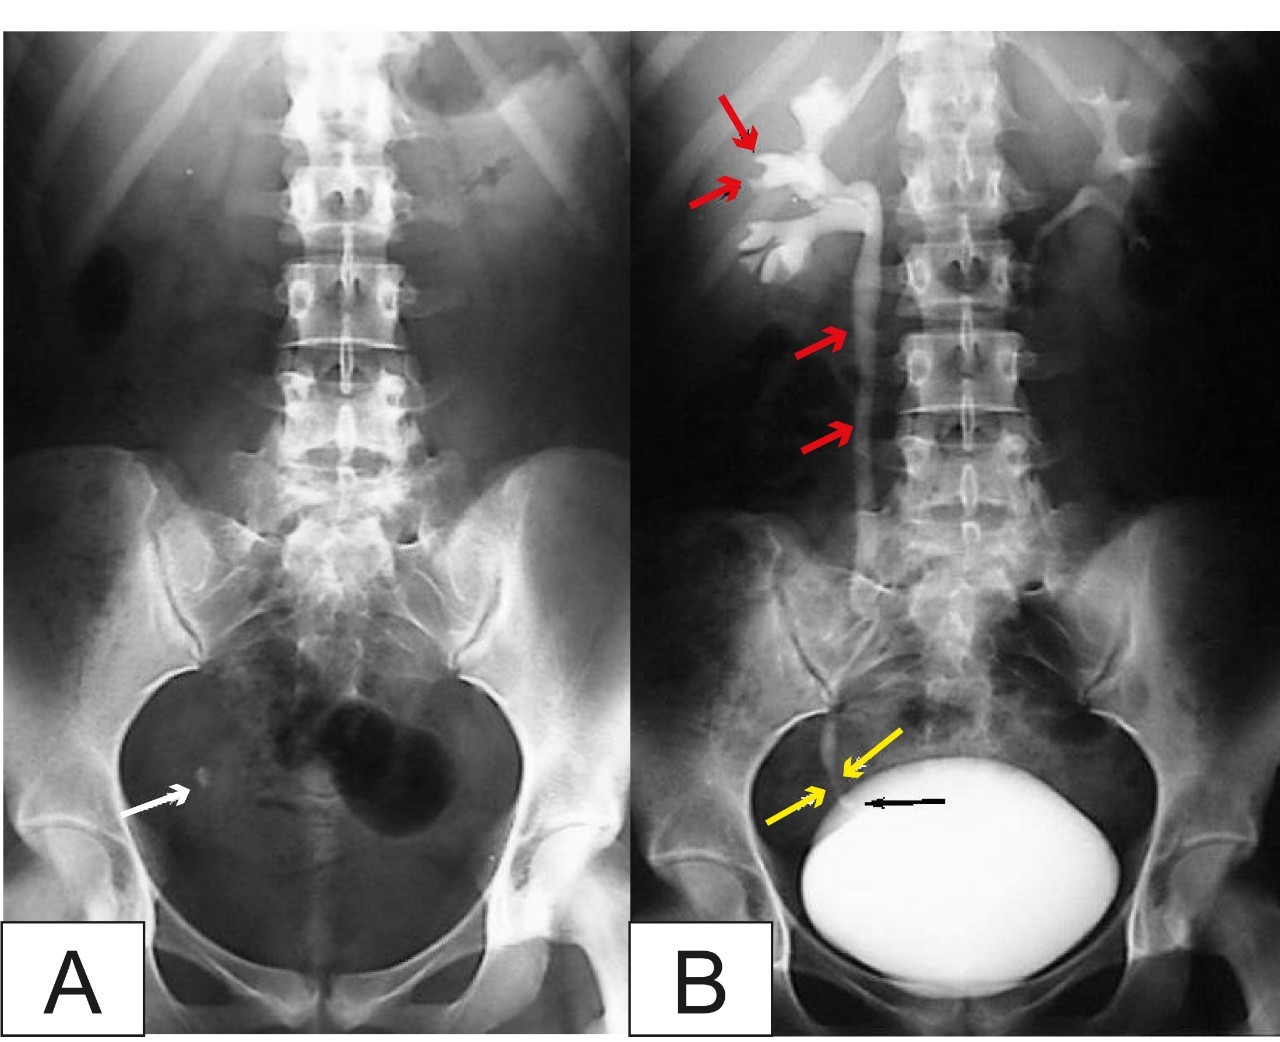

A 40-year-old woman in Taiwan (China) sought medical help for recurrent urinary tract infections. Her medical history showed that she drank enough water and did not hold her urine, but she had unusually excessive vaginal discharge. After being referred to the gynecology department, doctors discovered that she had endometrial cancer and had to undergo a hysterectomy to save her life.

The tragedy did not stop there. Her daughter, only in third grade, was also hospitalized due to persistent genital infections — and early menstruation. Tests revealed that the child had an advanced bone age and abnormally high estrogen levels. When doctors examined the family more closely, they noticed the opposite problem in the woman’s middle-school-aged son: typical male puberty signs such as body hair growth and a developing Adam’s apple had not appeared. The reason was excessive estrogen exposure in his body, which suppressed male hormones.

These abnormalities led doctors to suspect chemical exposure. After detailed questioning about the family’s lifestyle, a common habit emerged: the entire family frequently ate takeaway meals and drank hot soup stored in nylon plastic bags. Due to work commitments, the mother bought outside food almost daily and asked vendors to package hot food in plastic bags for convenience.

Subsequent tests showed that DEHP, a type of plasticizer (phthalate), was present in the family’s bodies at levels 3 to 5 times higher than safety limits.